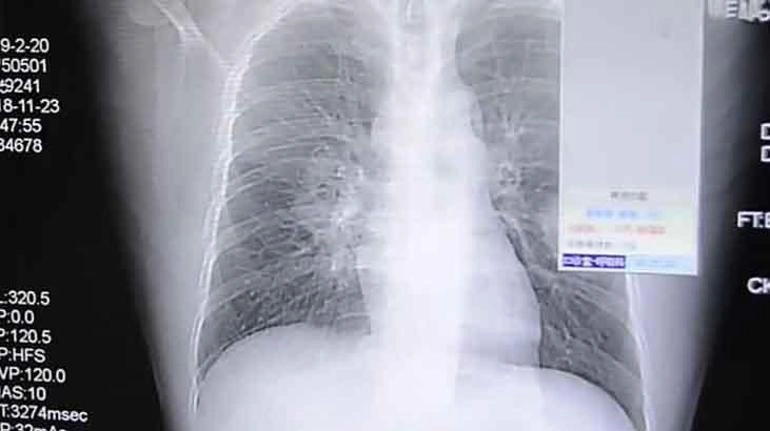

Sherg.az xəbər verir ki, hər şey Çinin cənub-qərbində yerləşən Çonqçinq şəhərində yaşayan bir kişinin hər gecə öskürək tutmaları keçirməsi ilə başladı. Xəstəxanaya aparılan adama həkimlər dərhal müdaxilə etdi. Bronxoskopiya nəticəsində orta yaşlı adamın sağ ağciyərində ciddi infeksiya olduğu müəyyən edildi. Lakin bu, adi infeksiya deyildi. Məlum oldu ki, o, rütubətli yerlərdə çoxalan Aspergillus adlı kif göbələyinin səbəb olduğu Aspergilloz xəstəliyinə yoluxub. Həkimlər xəstəliyin səbəbini araşdırarkən heyrətamiz bir nəticə ilə qarşılaşdılar. Çünki xəstəliyin mənbəyi onun corabları idi. İşdən sonra kirli corablarını iyləyən adamın corabları araşdırıldıqda, həmin göbələk növü ilə eyni olduğu aşkarlandı.

Lakin bu hal Çində ilk dəfə baş vermirdi. 2018-ci ildə ölkənin cənub-şərqində yerləşən Canqjou şəhərində yaşayan 37 yaşlı bir kişi də öskürək və sinə ağrısı şikayətləri ilə xəstəxanaya aparılmışdı. Səhiyyə işçiləri ilə söhbətində o, geyindiyi corabların qoxusuna asılılıq yaratdığını demişdi. Onun da ayaqqabısında yaranan sporlar ağciyərində infeksiyaya səbəb olmuşdu.